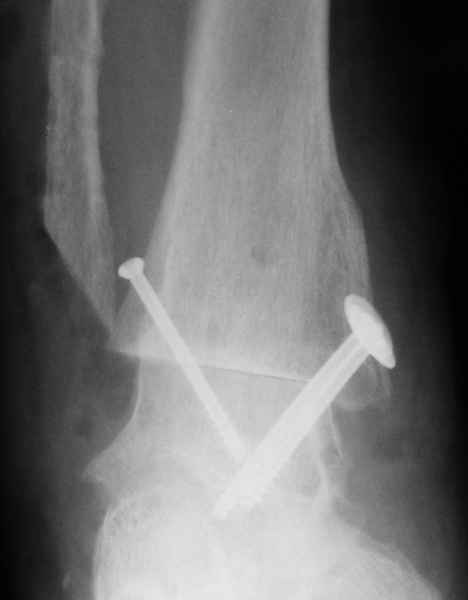

На фоне свищевой формы остеомиелита (скорее всего, речь идет об этом) о любой одноэтапной реконструктивной операции думать сложно. Если же все-таки решаться на одноэтапную операцию, то только убедившись, что гнойный процесс ограничивается внутренней лодыжкой. В этом случае возможен артродез с резекцией лодыжек (как на представленной рентгенограмме). Подобная операция позволяет относительно легко установить кости в оптимальное для артродеза положение, а также устранить гнойный очаг.